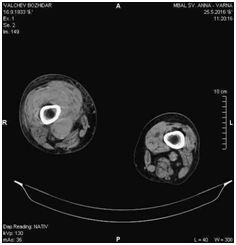

There were no significant blood test abnormalities, except elevated C-reactive protein. Electrolytes and renal function tests were normal. Performed color Doppler ultrasound of the lower leg vessels revealed an image with a greatest diameter of 38.32mm within the topography of the SFA, poorly-defined limits and mural thrombus. These characteristics suggested a ruptured aneurysm of the SFA (Figure 3). Computed tomography angiography (CTA) revealed ruptured aneurysm of right SFA with a diameter of 34mm (Figure 4 and 5).

Figure 4 CTA image showing an aneurysm of the right SFA.

Figure 5 CTA image showing an ruptured aneurysm of the right SFA.